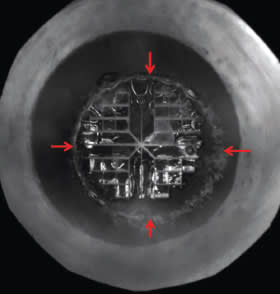

A 5 mm round anterior capsulotomy created by a femtosecond laser.